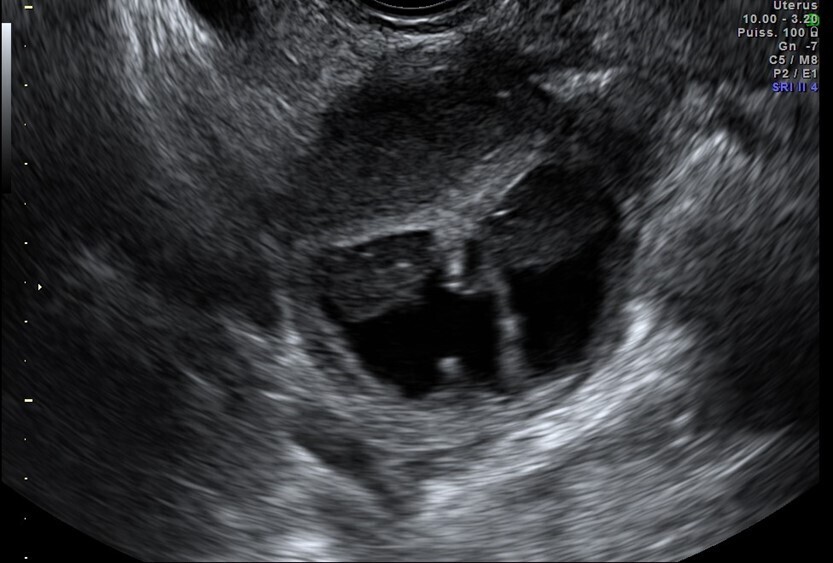

Vous faites une échographie pelvienne qui retrouve un utérus antéversé avec un endomètre épaissi de 5 mm, des ovaires droit et gauche sans anomalie. Il n’y a pas d’épanchement dans le cul-de-sac de Douglas.